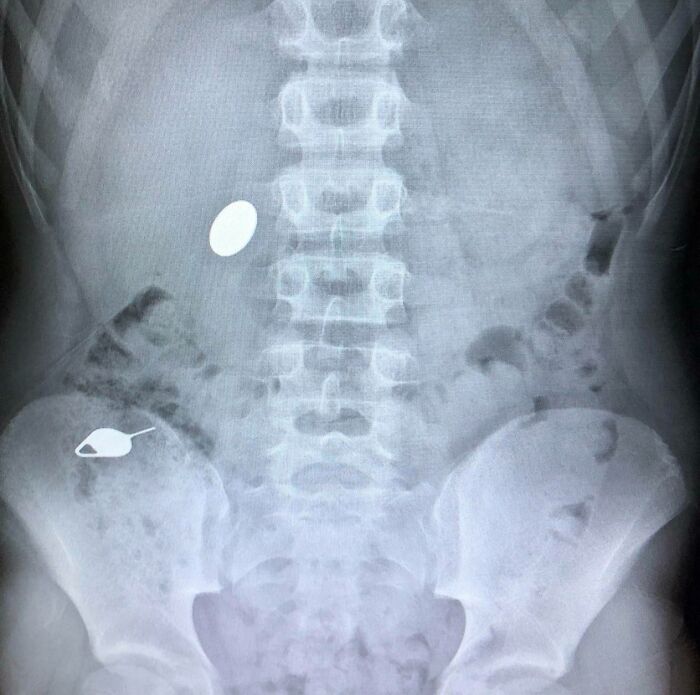

Mi hijo se tragó un centavo mientras le mostraba a su hermano pequeño cómo se había tragado accidentalmente una clave SIM el día anterior.

No entiendo. Eso es el pinchito que sirve para sacar la tarjeta del móvil??